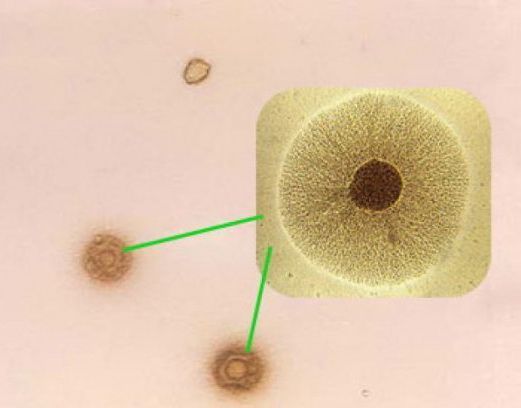

Чаще всего выделяют Ureaplasma urealyticum и Mycoplasma hominis из половых органов, которые хорошо растут на специальных питательных средах. Mycoplasma genitalium представляет собой сложный для выращивания вид, и для обнаружения этого вида требуется использование полимеразной цепной реакции или других молекулярно-биологических технологий.

Микоплазмы классифицируются в независимый класс Mollicute из-за уникальных биологических свойств, которые отличают их от бактерий. Они являются самыми мелкими из свободноживущих микроорганизмов, не имеют клеточной стенки, не окрашиваются по Граму, устойчивы к антибиотикам, подавляющим синтез клеточной стенки, и выращиваются на специальных питательных средах.

Классическим методом выявления генитальных микоплазм является метод посева, например, посев на питательные среды. Этот метод позволяет оценить количество микоплазм, содержащихся в исследуемом материале. Многие исследователи используют количественные критерии в диагностике, считая, что концентрация уреаплазмы более 104 микробных тел в одном мл или грамме выделений имеет диагностическое значение, тогда как более низкие концентрации не следует принимать во внимание, поскольку такое количество уреаплазмы может быть обнаружено в здоровые люди.

Посев исследуемого материала обычно проводят на твердые и жидкие питательные среды; предпочтительно использовать два образца почвы для каждого клинического материала. В качестве исследуемого материала используются материалы из влагалища, цервикального канала шейки матки, уретры, мочи, спермы, срезанные материалы, а также околоплодные воды, плацента, слизь носоглотки. Одновременно проводится посев на среды с разведениями антибиотиков для определения их чувствительности.